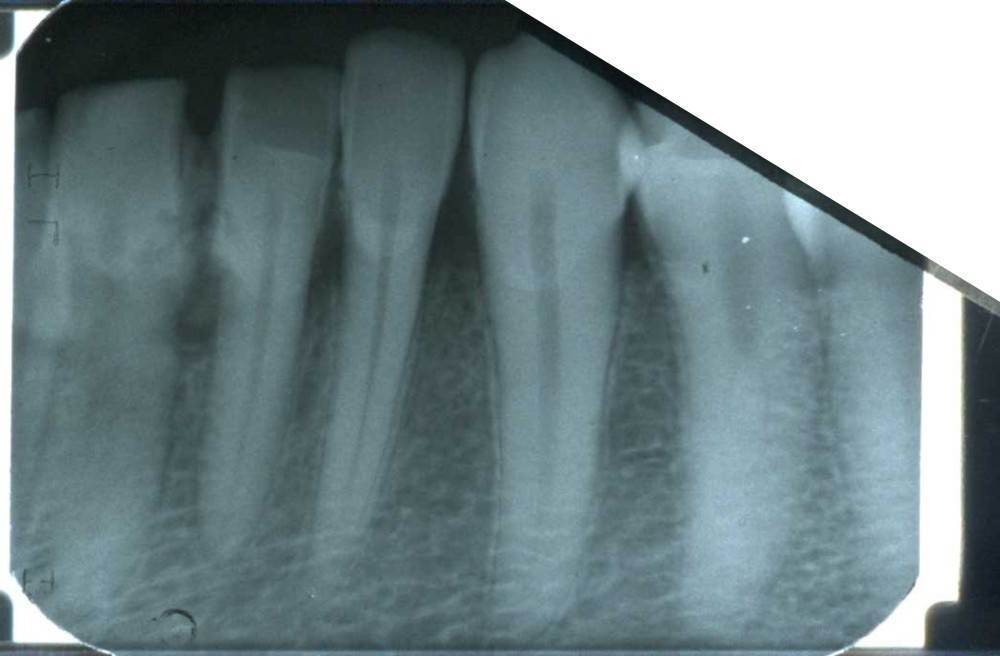

Sergey-010101 Опубликовано 5 октября, 2025 Поделиться Опубликовано 5 октября, 2025 (изменено) Здравствуйте. У меня на нескольких передних зубах большие камни, рецессия десны, на миллиметров 5-6 камень опускается спереди и сзади зуба. В одной стоматологии предложили чистку ручными инструментами. В другой аппаратом Вектор. Что являет более безопасным для чистки камней на корнях? Какой вариант выбрать? Вектор вроде ультразвук использует. А пишут что ультразвуком камни на корнях вредно чистить. Есть ли у Вектора какие то варианты? Насадки? Если выбрать этот способ есть моменты которые нужно уточнить? Обратить более подробное внимание. Изменено 5 октября, 2025 пользователем Sergey-010101 Ссылка на комментарий

Sergey-010101 Опубликовано 5 октября, 2025 Автор Поделиться Опубликовано 5 октября, 2025 И что делать если будут шататься потом, чтобы сохранить? Как нарастить десну кость? Немного есть мнения что есть риск потери. Но в целом несколько врачей сказали что могут даже не шататься. Убыль кости есть на 2-3 мм в некоторых местах, но корень более чем на половину в кости. Ссылка на комментарий